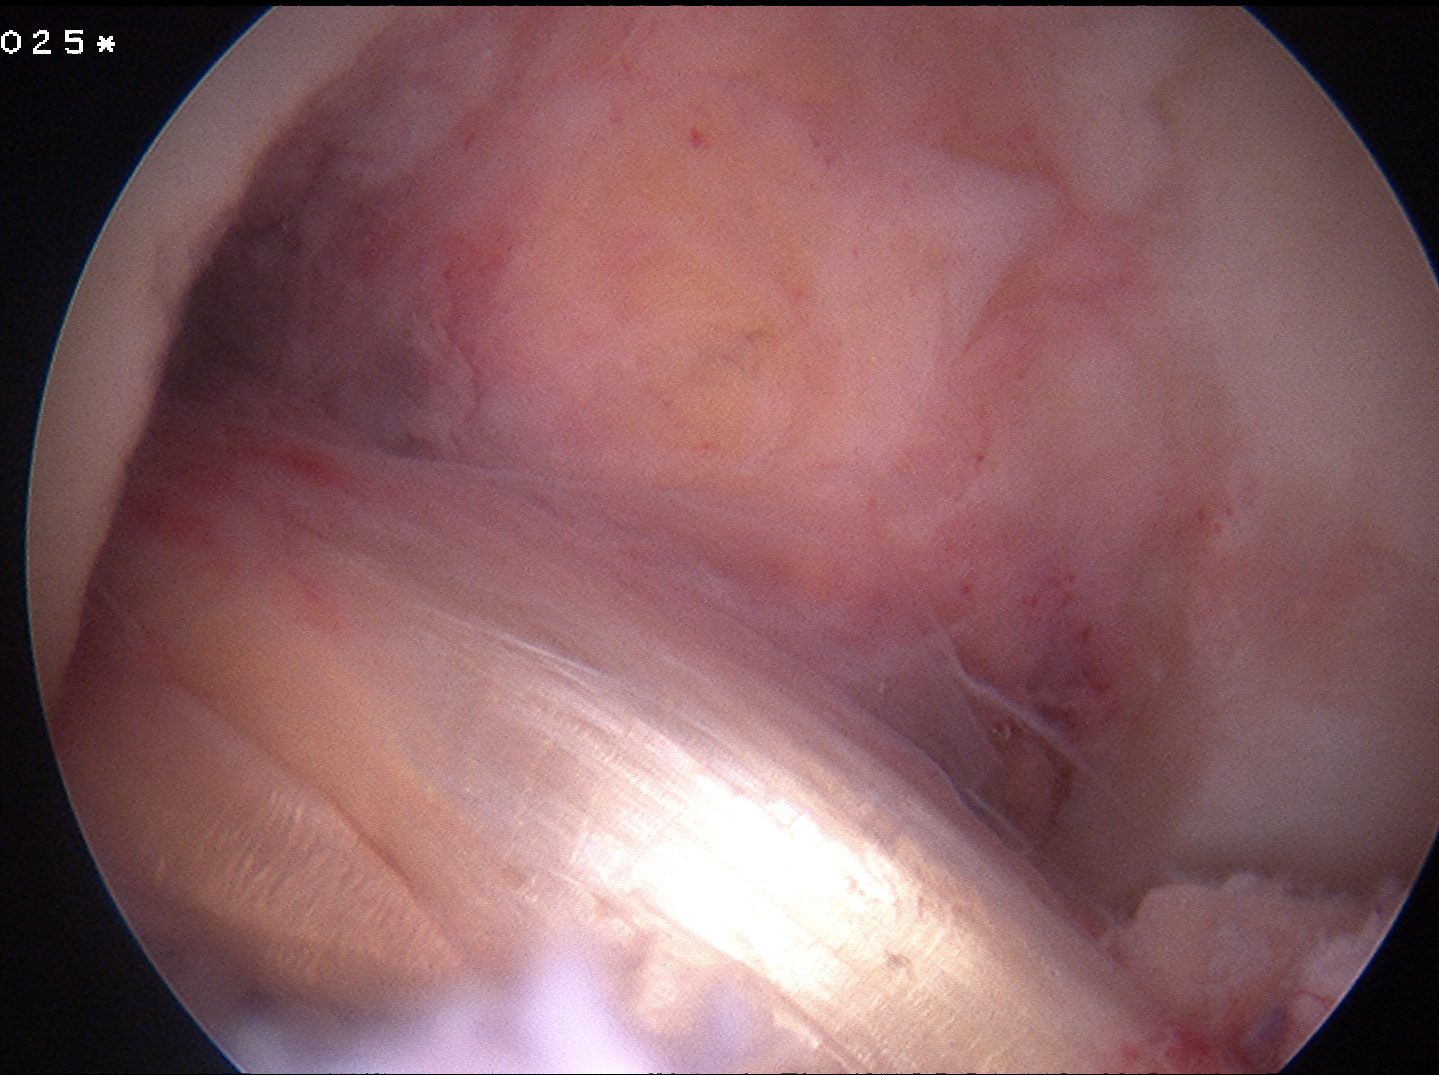

Failed ACL with tibial tunnel too posterior and with lysis

Tunnels debrided / redrilled and synthetic bone plugs inserted